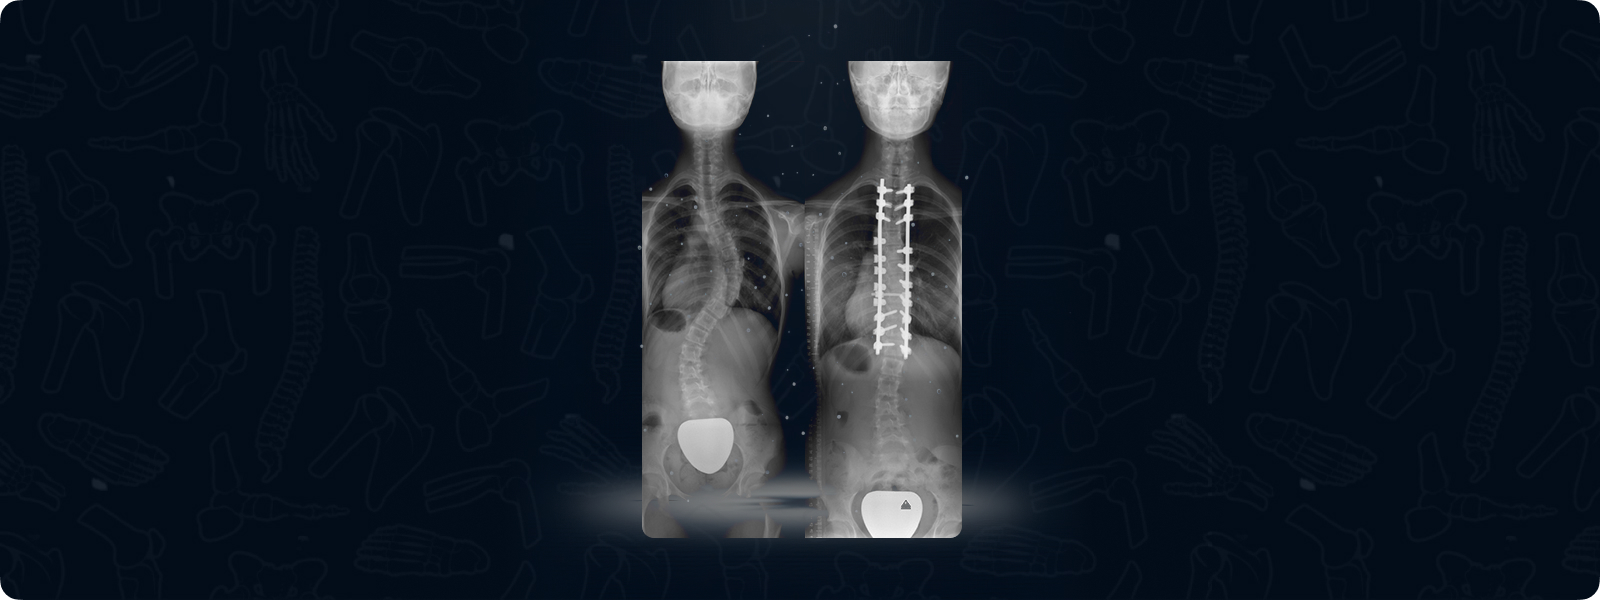

Scoliosis can involve a single curve, however, double or triple curves may be observed. The traditional operative treatment for scoliosis is posterior instrumented fusion. This involves achieving a bony union in the operative field, therefore stopping the motion in the operated vertebra.

Selective fusion is a method that preserves motion segments. In selective fusion, only one curve is operated in a patient with double or triple curves, and the other curves are spontaneously corrected. This is usually done by operating the thoracic spine and correcting the lumbar spine spontaneously allowing ­for preservation of motion.